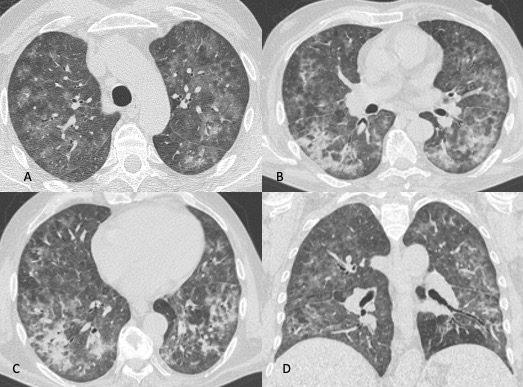

I reperti TCAR sono diversi, in genere nella fase iniziale si documenta la presenza di “vetro smerigliato” diffuso a distribuzione simmetrica che in alcuni casi mostra prevalente distribuzione perilare con risparmio delle zone sub pleuriche e predilezione per i lobi superiori. In seguito, si sovrappongono ispessimento dei setti interlobulari (“crazy paving” pattern), aree di consolidazione parenchimale, noduli e formazione di pseudocisti sub pleuriche (non sempre presenti) che possono andare incontro a rottura provocando pneumotorace spontaneo (Figure 4 e 5).

Figura 4: Donna di 78 anni con diagnosi di Linfoma di Hodgkin. Le immagini assiali (A-B-C) mostrano il parenchima polmonare normale. Un anno dopo la paziente giunge al Pronto Soccorso per un rapido peggioramento della funzionalità respiratoria, dispnea e tosse. La TCAR eseguita alcuni giorni dopo il ricovero nel reparto di Malattie Infettive (D-E-F) mostra la presenza in entrambi i polmoni di "vetro smerigliato" diffuso con relativo risparmio delle zone sub-pleuriche e la comparsa di formazioni pseudocistiche nel lobo superiore sinistro (frecce in D ed E). L’ipotesi formulata e poi confermata dal laboratorio è stata quella di polmonite da Pneumocystis Jirovecii.

Figura 5: Uomo di 68 anni immunocompromesso giunge al Pronto Soccorso per IRA. La TCAR eseguita all’ingresso (immagini assiali A-B-C e la ricostruzione MPR sul piano coronale D) mostrano "vetro smerigliato" diffuso e simmetrico in entrambi i polmoni con relativo risparmio delle aree sub-pleuriche solo in alcune zone nel polmone. L’ipotesi diagnostica formulata è stata quella di polmonite interstiziale. Le indagini di laboratorio hanno in seguito rivelato che l’agente patogeno responsabile del quadro flogistico era lo Pneumocystis Jirovecii. La diagnosi differenziale tra le varie cause di iperdensità parenchimale nei pazienti con IRA non è semplice soprattutto quando le alterazioni sono molto estese e diffuse.